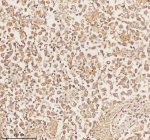

Immunohistochemical staining of PLBD2 using anti-PLBD2 antibody. PLBD2 was detected in a paraffin-embedded section of human lung adenocarcinoma tissue. Heat mediated antigen retrieval was performed in EDTA buffer (pH 8.0, epitope retrieval solution). The tissue section was blocked with 10% goat serum. The tissue section was then incubated with 2 ug/ml rabbit anti-PLBD2 antibody overnight at 4oC. Peroxidase Conjugated Goat Anti-rabbit IgG was used as secondary antibody and incubated for 30 minutes at 37oC. The tissue section was developed using an HRP secondary and DAB substrate.